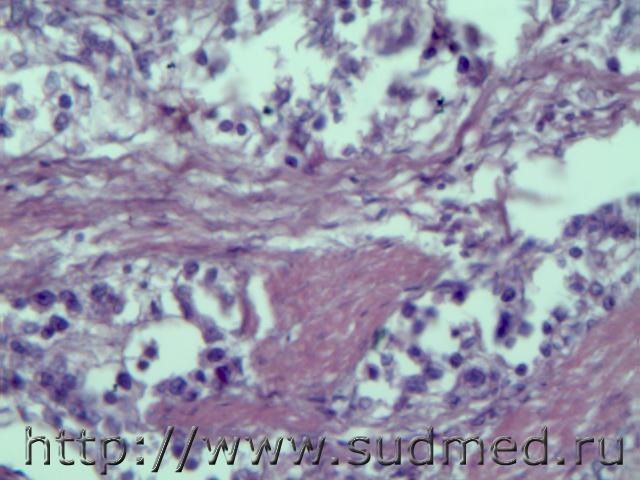

Тромбоэмболий легочных артерий.

1.Смешанный тромб в просвете мелкой ветви правой легочной артерии.

2.Геморрагический инфаркт лёгкого.